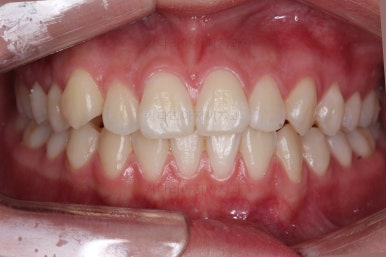

교합도 안정되는 것을 확인했고, 치열도 만족할 수준으로 디테일한 정리를 해줬어요.

왼쪽이 치료 초기의 교합 모습, 오른쪽이 치료 마무리 시점의 교합입니다.

빈틈이 많았던 교합이 많이 개선된 것이 보이시죠?

이러한 이유 때문에 전체교정이 필요했답니다.

약간의 정리 후, 마무리를 하였습니다.

총 치료기간은 13개월이 걸렸네요.